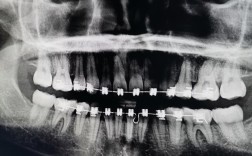

种牙的核心在于技术与医生经验的结合,美奥口腔在这两方面优势显著,在技术层面,美奥引进国际先进的数字化种植系统,通过3D口腔扫描、CBCT影像分析,精准测量牙槽骨的密度、厚度及神经血管位置,实现种植方案的个性化设计,其采用的微创种植技术,仅需3-8mm微小切口,就能完成种植体植入,手术时间缩短至30分钟左右,且术中出血少、术后肿胀轻,大幅降低患者恐惧感,针对牙槽骨条件不佳的患者,美奥还开展骨增量技术(如GBR骨引导再生、上颌窦提升等),为复杂种植病例提供解决方案,让更多缺牙患者重获种牙机会。

医生团队是种植牙成功的另一关键,美奥口腔汇聚了一批临床经验丰富的种植专家,团队医生均拥有10年以上种植经验,累计完成种植案例超万例,他们擅长处理各类复杂种植病例,如半口/全口种植、即刻种植、即刻负重等,能根据患者的口腔状况、年龄及需求,制定“一人一策”的种植方案,针对中老年患者常见的牙槽骨萎缩问题,美奥医生会结合动态导航技术,实现种植体的精准植入,确保种植体与骨组织紧密结合,提高长期成功率。